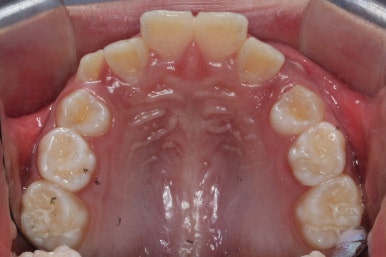

초진 시의 모습입니다.

11살의 어린이였기에 몇 군데 아직 유치가 남아있었습니다. 영구치가 모두 나오지 않았죠. 덧니가 있고 치열이 고르지 못하더라도 일반적으로 영구치가 더 나온 후에 연산동덧니교정 하는 것을 권해드립니다.

아직 유치가 몇 개 남아있기에 장치가 전체적으로 부착되지 않습니다. 우선 앞니 4개만 먼저 치열을 맞추고 위쪽 어금니는 후방 이동을 해주면서 교합을 맞추며 덧니가 내려올 공간을 확보합니다.

영구치도 이제 거의 다 나왔고 삐뚤한 다른 부분도 전체 메탈장치를 붙였습니다.